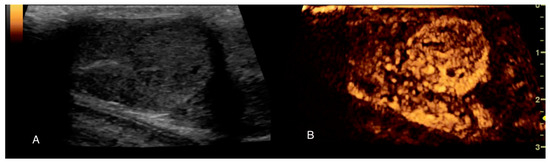

Imaging of Testicular Tumours